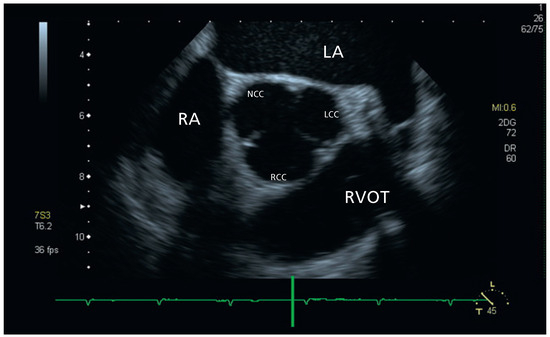

Aortic Valve Rupture Due to a Motorcycle Accident

by Daniela Vocke, Igal Moarof, Peter Matt and Pablo Anabitarte

Cardiovasc. Med. 2011, 14(6), 192; https://doi.org/10.4414/cvm.2011.01597 - 29 Jun 2011

Viewed by 93

Abstract

A 62-year-old male patient was admitted as a result of a motorcycle accident [...] Full article